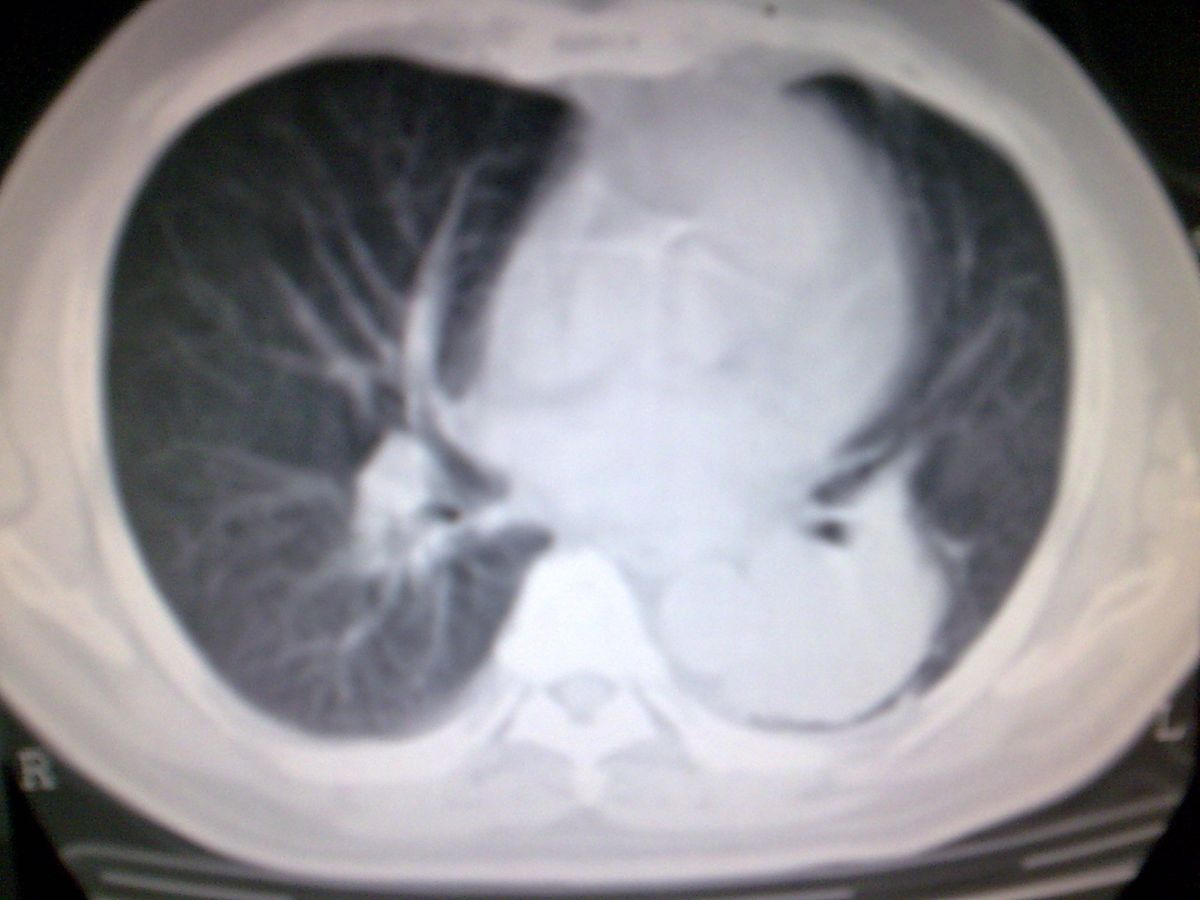

标题: CT19282:男性,70岁,咳血, [打印本页]

标题: CT19282:男性,70岁,咳血,

图片少了些,考虑周围性肺癌

考虑周围性肺癌

周围型肺癌。

考虑左下肺周围性肺癌。

考虑左下周围型肺癌可能性大。

考虑左肺下叶周围型肺癌可能。